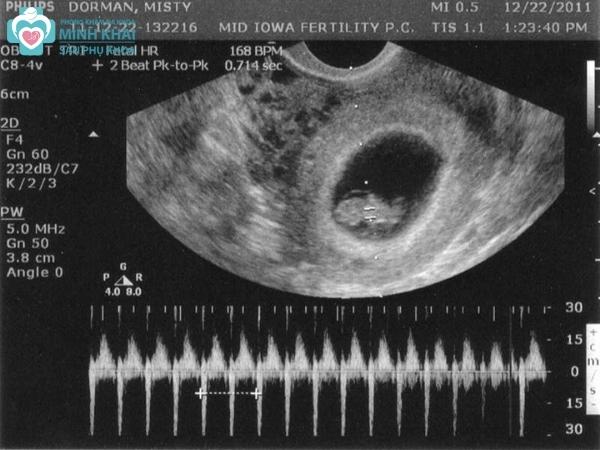

Siêu âm thai 2D kiểu M thường được áp dụng để siêu âm tim thai. Nó giúp thu lại hình thái, chuyển động của em bé trong bụng mẹ nhờ sóng âm vang chữ A và màn hình quét ngang theo thời gian thực.

Đo nhịp tim thai